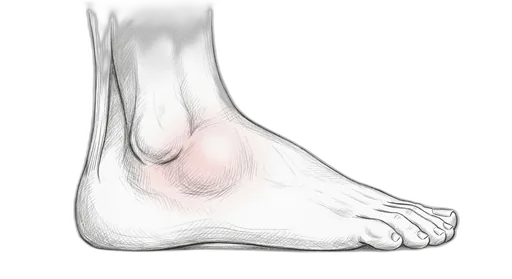

Foot & Ankle Exercise Guide

Choose your condition below to get started with exercises and stretches designed by Dr. Patish.

Pick your condition below, and you'll find your personalized exercise program — with medical illustrations, step-by-step instructions at three intensity levels, and clear guidance on when to call our office. Every protocol here is the same one Dr. Patish prescribes to patients in the clinic.

Heel & Arch

Achilles & Calf

Forefoot & Toes

Fractures

Other